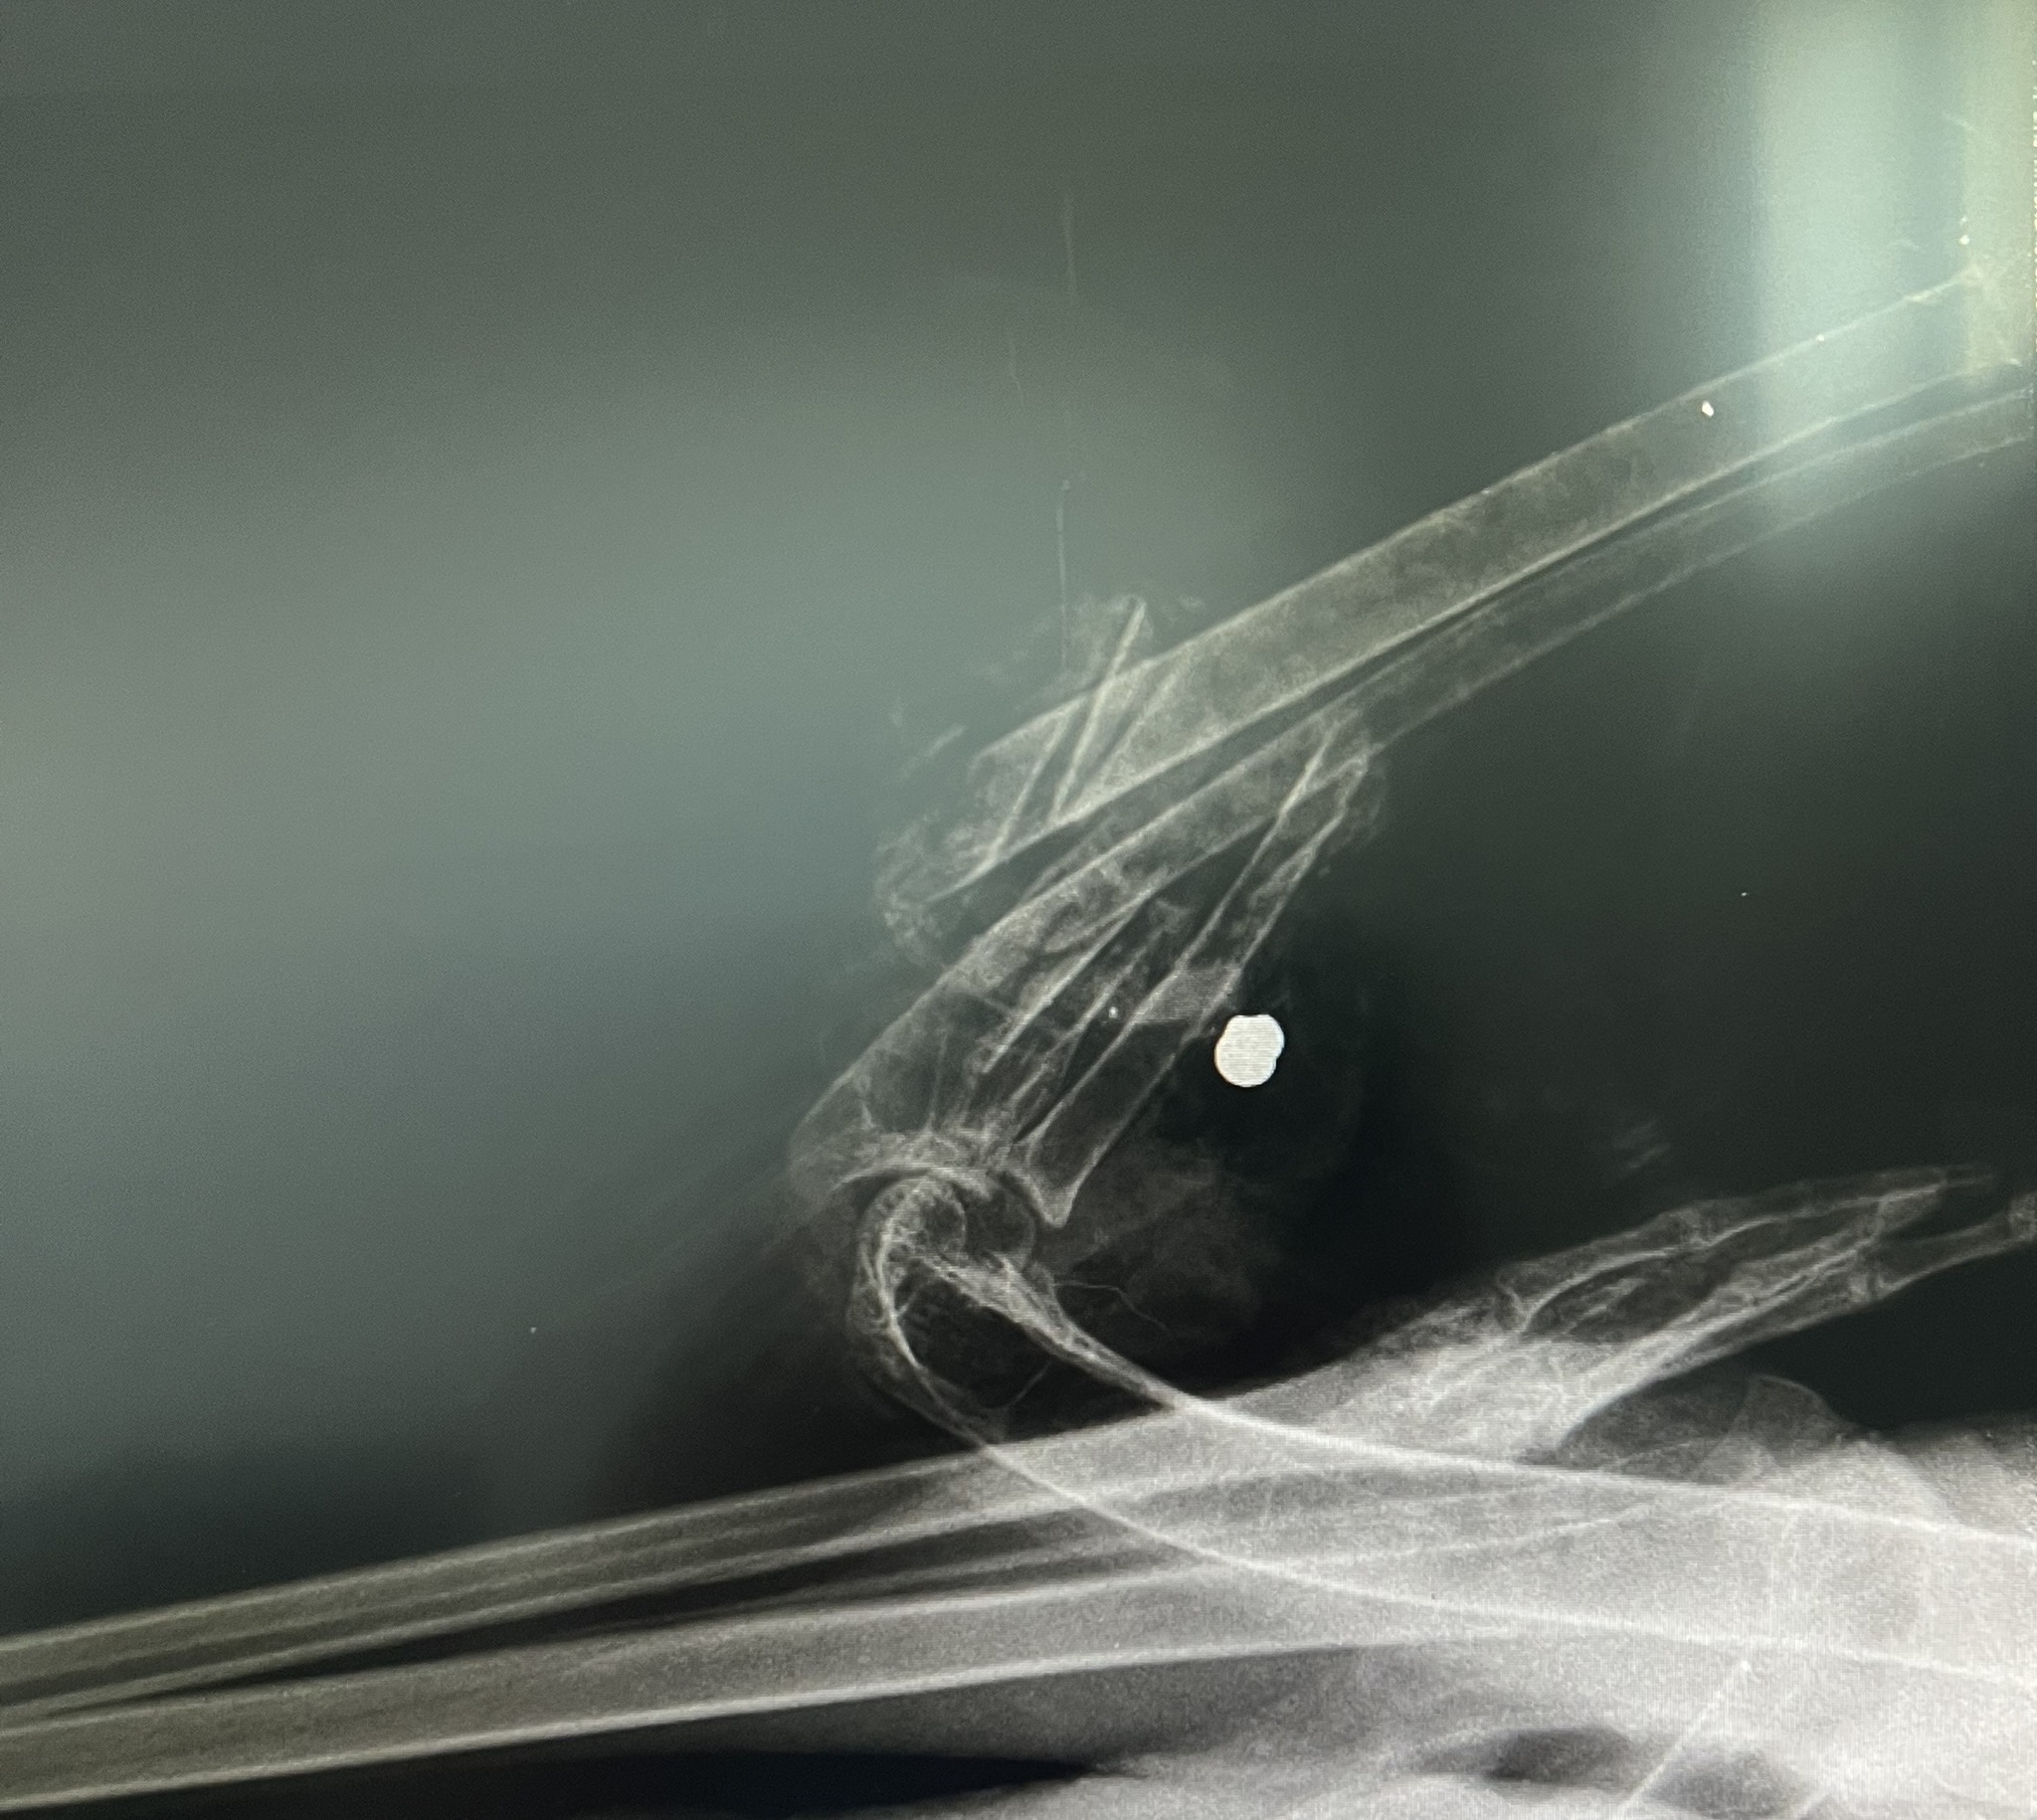

| Primer ustreljene bele štorklje (Ciconia ciconia) v Slovenski Bistrici Dne 14. 8. 2025 je bila v ambulanto nacionalnega zatočišča za prostoživeče živali Golob d.o.o. na Muti sprejeta odrasla bela štorklja, najdena na območju Slovenske Bistrice. Klinične ugotovitve ob sprejemu: • odrasel osebek v dobri telesni kondiciji (telesna masa 3.400 g, dobro razvite prsne mišice, normalna operjenost letalnih in repnih peres, ter nepoškodovana obrisna krovna peresa telesa, zdravi medenični končini), • odprti zlom komolčnice in koželjnice leve peruti, • obsežna raztrganina letalnih mišic z izgubo tkiva, • sekundarna bakterijska infekcija poškodovanega tkiva, razvoj miaze in vlažne gangrene (Gangrena humida), • RTG-diagnostika je potrdila prisotnost svinčene krogle v proksimalnem segmentu podlakti, ki je povzročila strelno lezijo z obsežnim poškodovanjem kostnih in mišičnih struktur. Sekundarno je zaradi padca z obcestne svetilke nastopila dodatna travmatska poškodba peruti. Poškodbe so povzročile obsežno nekrozo, izgubo krvi, septično in hipovolemično stanje s šokom, kar je bil neposredni vzrok pogina. Oskrba ob sprejemu: Izvedena je bila stabilizacija s tekočinsko terapijo, protibolečinska in protivnetna terapija, antibiotično zdravljenje, toaleta rane ter hranjenje po sondi. Kljub intenzivni oskrbi je žival zaradi obsežnih poškodb poginila. Primer je bil skladno s protokolom predan v nadaljnjo obravnavo na Veterinarsko fakulteto (raztelezba). Opomba: Do tega trenutka primera nismo javno komentirali, saj smo želeli dosledno spoštovati strokovne in pravne protokole. Prvotne informacije so bile nemudoma posredovane pristojnim organom. Naše stališče: Strel v belo štorkljo, ki je v Sloveniji in Evropi strogo zavarovana vrsta, razumemo kot nesprejemljivo dejanje, ki nima nikakršnega opravičila. Takšna ravnanja pomenijo neposredno ogrožanje prostoživečih živali ter hkrati kršitev nacionalne in evropske zakonodaje. Kot strokovna institucija menimo, da morajo biti takšna dejanja dosledno preiskana, odgovorne osebe pa ustrezno sankcionirane. Naš namen ni le obravnava posameznih primerov, ampak tudi opozarjanje družbe, da ima zaščita prostoživečih živali širši pomen za ohranitev biotske raznovrstnosti in naravne dediščine Slovenije. |